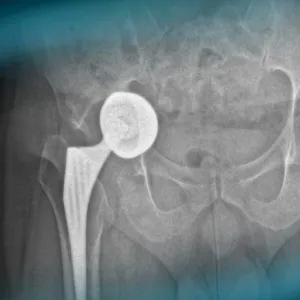

The goals of this clinical case are to discuss the different therapeutic options in case of acetabular loosening in total hip arthroplasty, to propose an innovative technique, and to see outcomes after revision hip surgery.